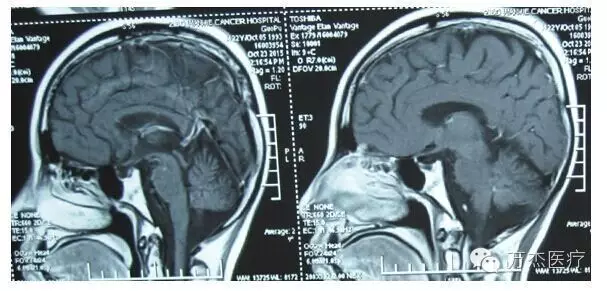

典型病例(髓母细胞瘤):

QQ图片20160531113013

治疗前

QQ图片20160531113042

治疗结束时

QQ图片20160531113100

治疗后一月

QQ图片20160531113117

治疗后10年